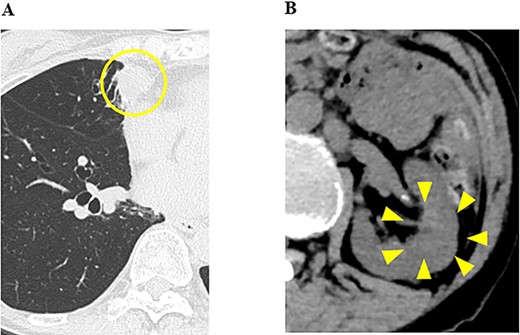

Ten months after the start of lenvatinib, CT showed a decrease in the sizes of pulmonary metastases (Fig. 3A) and renal metastasis (Fig. 3B) (tumor reduction rate: 45%). Remnant thyroid resection was performed and followed by RAI therapy with 100 mCi. In 131I scintigraphy, some lung metastases showed radioiodine uptake, whereas others did not. Radioiodine uptake was also observed in the left renal tumor, but not in the right kidney (Fig. 4A); therefore, the left renal tumor was finally confirmed as renal metastasis of PTC. Since the sizes of pulmonary and renal metastases both increased after the RAI therapy (tumor growth rate: 71%) (Fig. 4B), the administration of lenvatinib was resumed from a dose of 4 mg/day. After resuming lenvatinib, she has been in SD status for 6 months.

131I scintigraphy and CT images of the chest and abdomen after the second surgery; (A) in 131I scintigraphy, some lung metastases showed radioiodine uptake, whereas others did not. Radioiodine uptake was also observed in the left renal tumor, but not in the right kidney; left: RAI scintigraphy, right: SPECT–CT, P: pulmonary metastases, R: renal metastasis; (B) pulmonary and renal metastases both increased in size.